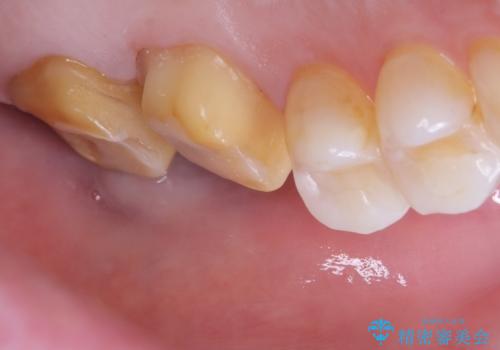

- 主訴:詰め物と歯の奥が側の境目に物がいつも溜まってしまう

保険適応のメタルインレーと歯質との間に不適合な箇所を認め、補綴物のやり替えでの治療となりました。インレーからクラウンへ補綴物の形態を変更し、素材は清掃性・適合性・審美性の点からセラミッククラウンでのやり替となりました。

レントゲン上にて、左上6番遠心にインレーと歯質の不適合を認めます。

健全歯質の残存量から、クラウンでのやり替えを提案しオールセラミッククラウン(スタンダード)でのやり替えとなりました。